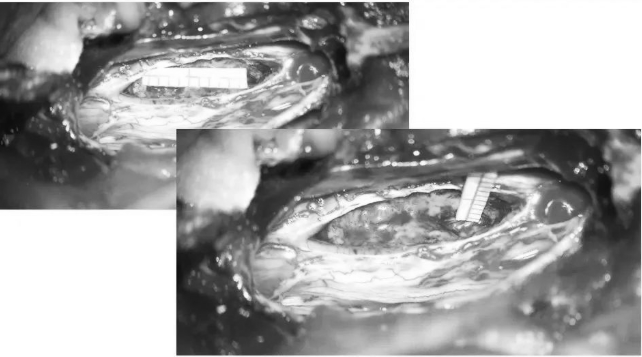

▼取下部分T5、T6椎板

▼术中超声定位海绵状血管瘤(白色)

▼术中超声显示髓内海绵状血管瘤超出骨窗大小,向T7方向生长,继续磨除部分T7椎板,扩大暴露范围

▼沿后正中切开,即可见含铁血黄素沉积带及陈旧性血凝块

▼用细致的双较或者剥离子沿含铁血黄素沉积带,分离海绵状血管瘤并电凝切断供血分支血管

▼逐步显露血管瘤腹侧面

▼血管瘤完整取出

▼测量瘤腔大小,明确肿瘤全切

▼用Proline缝线间断缝合软脊膜,封闭瘤腔,水密缝合硬脊膜